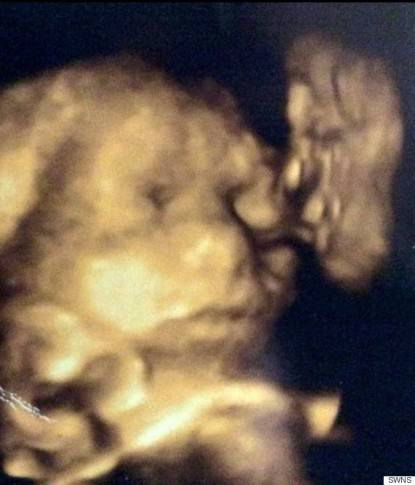

Le sue labbra sono corrugate come se si accingesse a darle un bacio sulla guancia. Si possono vedere gli occhi, il naso e la bocca”.

“Noi non riuscivamo a crederci, era come se cercasse di darle la sua benedizione nel grembo. L’ho trovato di grande conforto, ho tanti bei ricordi di mio nonno”.

Unimamme, ormai con le ecografie 4D possiamo davvero vedere i volti dei bimbi dal vivo, ma la foto mostrata da questa donna solleva davvero diversi interrogativi.

Voi cosa ne pensate dell’ecografia in 4D? Vedete anche voi il volto di una persona o  pensate sia solo il frutto di suggestione?